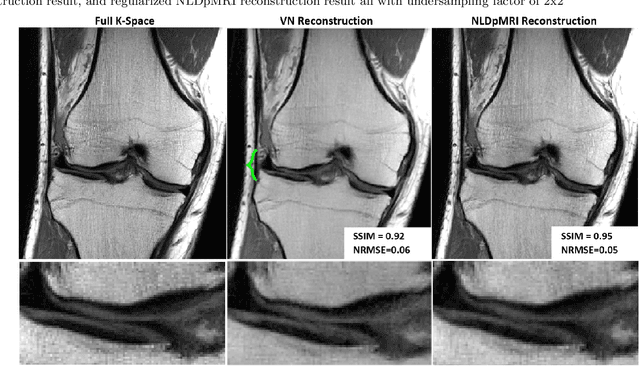

Abstract:Fast data acquisition in Magnetic Resonance Imaging (MRI) is vastly in demand and scan time directly depends on the number of acquired k-space samples. The most common issues in any deep learning-based MRI reconstruction approaches are generalizability and transferability. For different MRI scanner configurations using these approaches, the network must be trained from scratch every time with new training dataset, acquired under new configurations, to be able to provide good reconstruction performance. Here, we propose a new parallel imaging method based on deep neural networks called NLDpMRI to reduce any structured aliasing ambiguities related to the different k-space undersampling patterns for accelerated data acquisition. Two loss functions including non-regularized and regularized are proposed for parallel MRI reconstruction using deep network optimization and we reconstruct MR images by optimizing the proposed loss functions over the network parameters. Unlike any deep learning-based MRI reconstruction approaches, our method doesn't include any training step that the network learns from a large number of training samples and it only needs the single undersampled multi-coil k-space data for reconstruction. Also, the proposed method can handle k-space data with different undersampling patterns, and different number of coils. Unlike most deep learning-based MRI reconstruction methods, our method operates on real-world acquisitions with the complex data format, not on simulated data, real-valued data, or data with added simulated-phase. Experimental results show that the proposed method outperforms the current state-of-the-art GRAPPA reconstruction method.